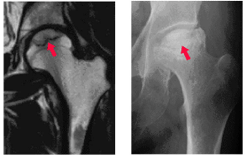

突然の痛みで発症することが多く、初期の場合はレントゲン写真などではわからないことがあるため、見逃されている例も少なくありません。今回は大腿骨頭壊死について簡単に説明いたします。

大腿骨頭壊死は、骨が死んでしまうだけでは症状はありません。

症状が出るのは、死んだ骨が崩れて大腿骨頭がつぶれてしまった時です。

急に足の付け根(股関節)の痛みが出るのが特徴的な症状となります。